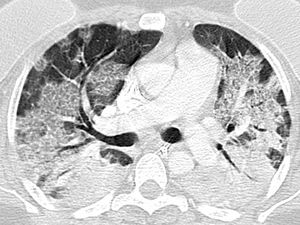

Indeterminate classification (Fig. 3) as a positive test for COVID-19 pneumonia, with an estimated sensitivity of 36.1% (95% CI 35.8%–38.9%), a specificity of 80.5% (95% CI 79.2%–80.7%), an AUC of 0.583 (95% CI 0.579–0.598), a PPV of 64.1% (95% CI 56.1%–71.2%), and an NPV of 56.2% (95% CI 51.6%–60.7%).